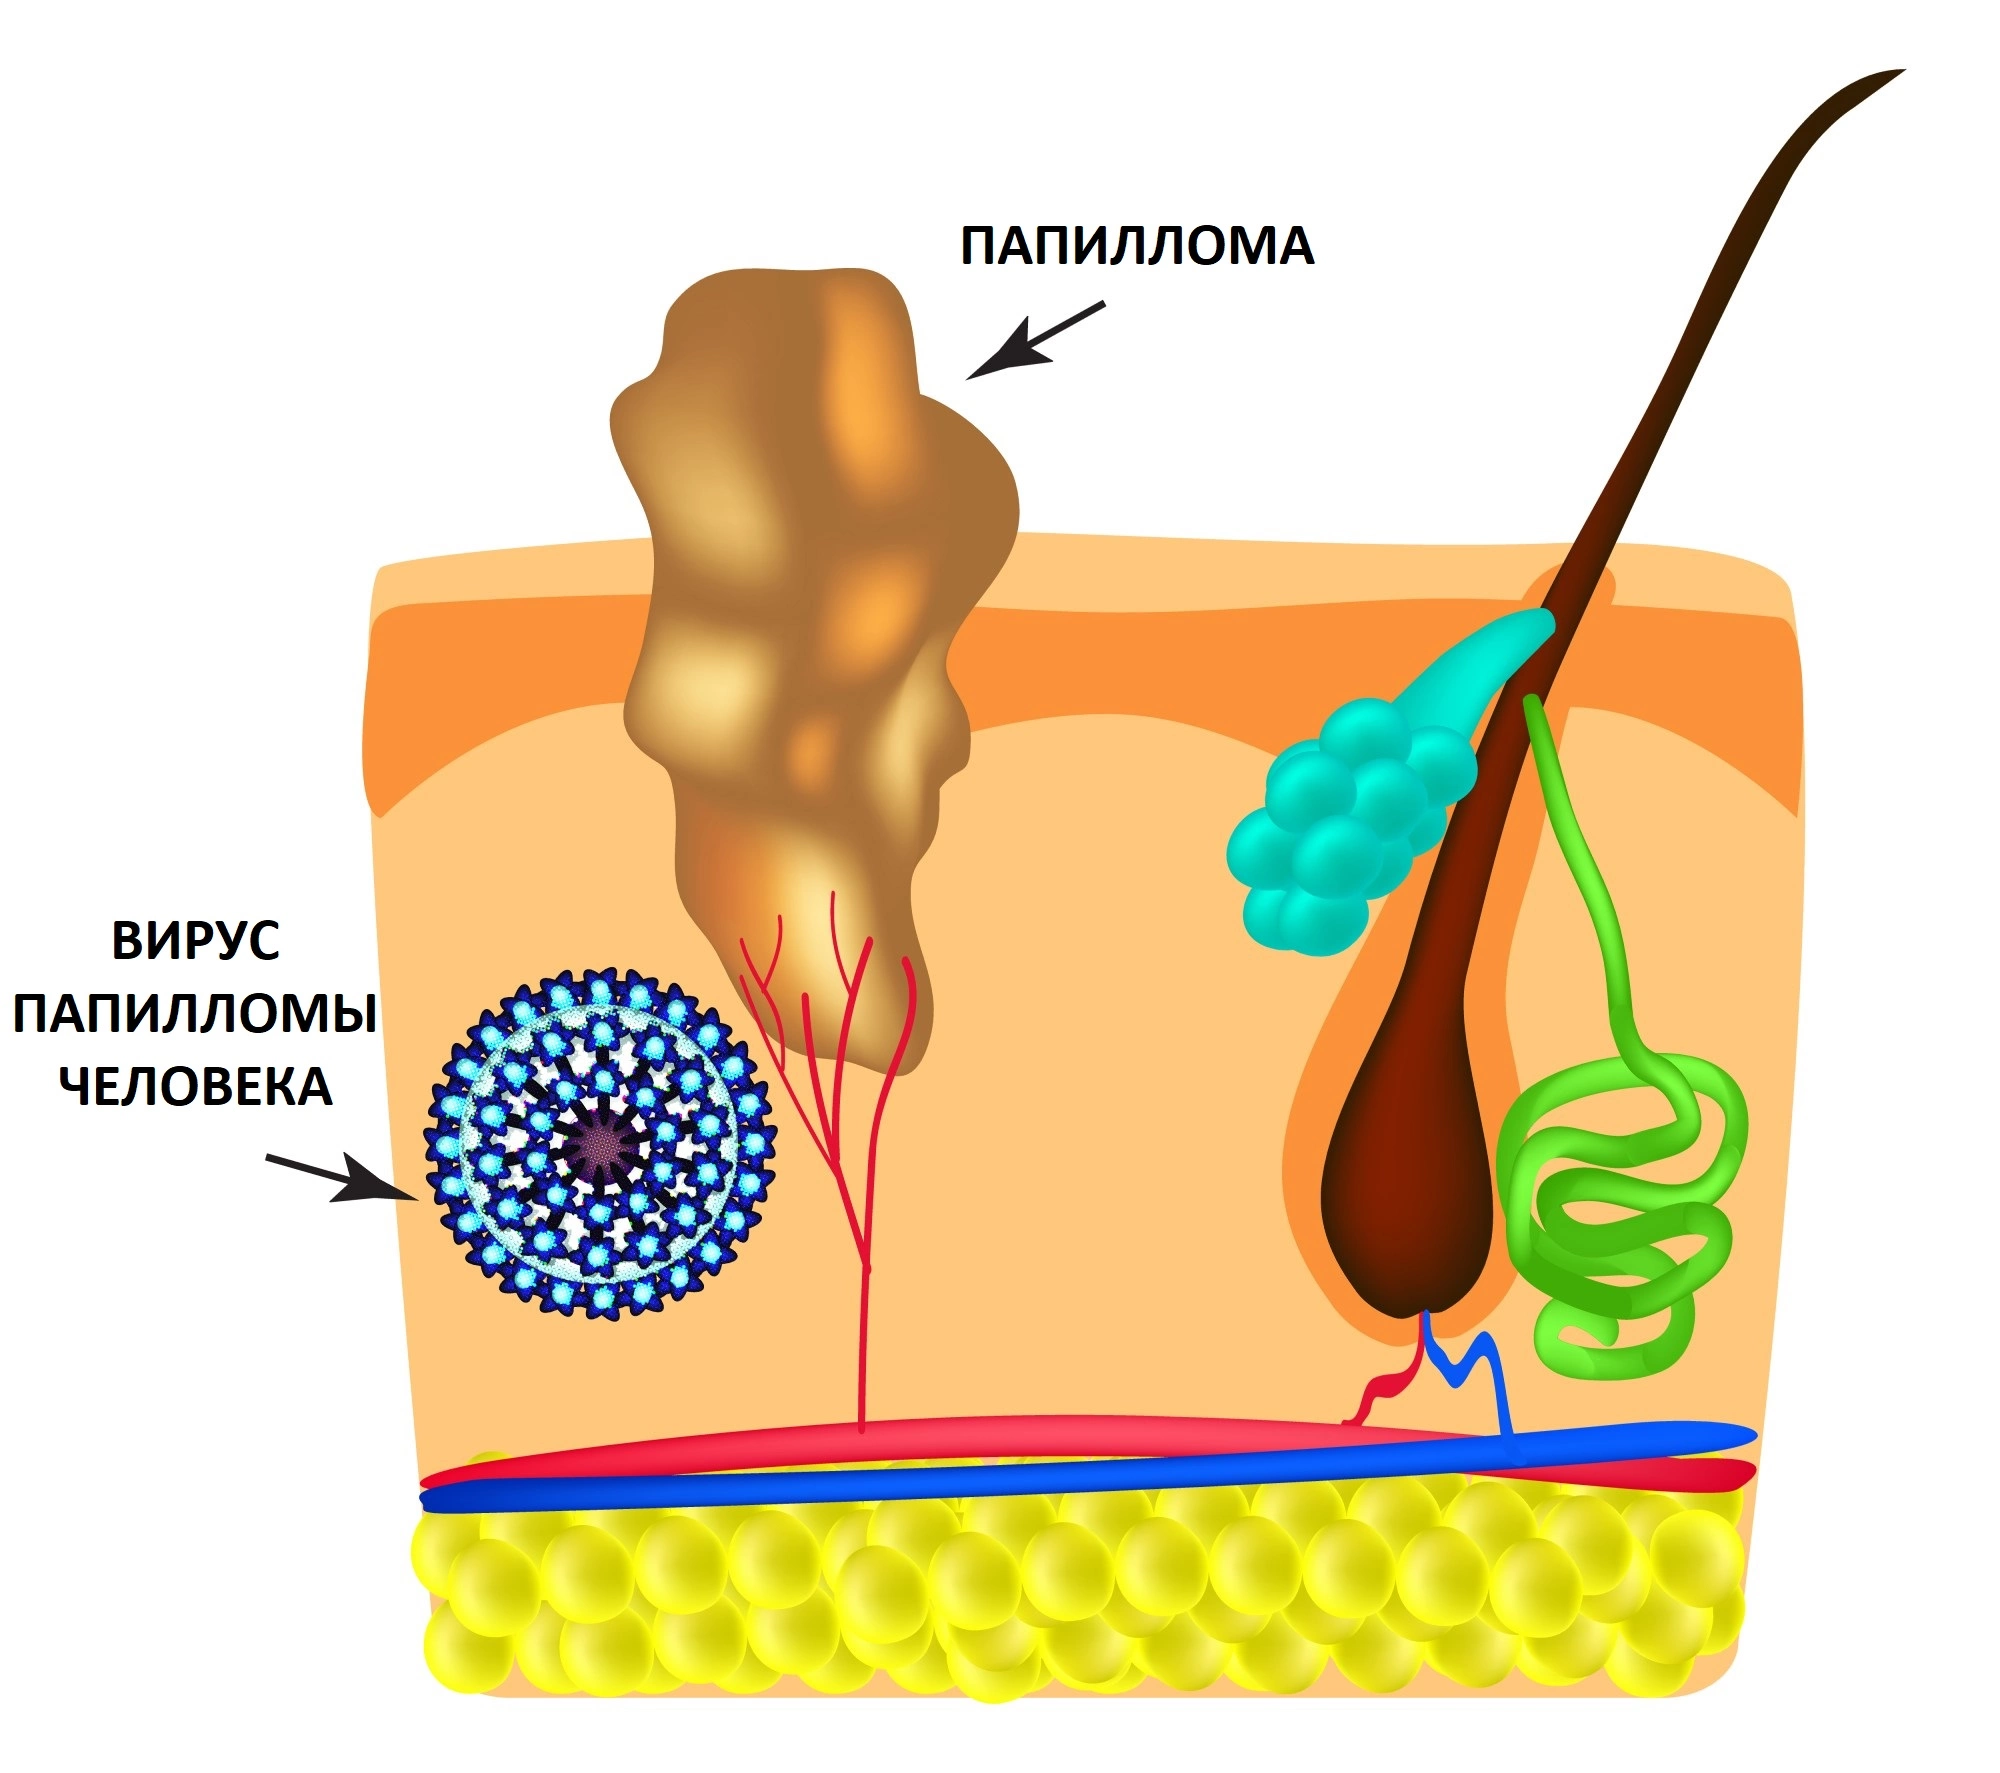

Кондиломы - это одно из самых распространенных заболеваний, передающихся половым путем. Они вызваны вирусом папилломы человека (ВПЧ) и могут появляться на внешних половых органах, анусе, ротовой полости и других областях тела.

Симптомы кондилом могут варьироваться, и визуальное представление этого заболевания может быть различным. Некоторые кондиломы выглядят как небольшие бугорки или бородавки, в то время как другие могут иметь форму плоских пятен или цветных наростов.